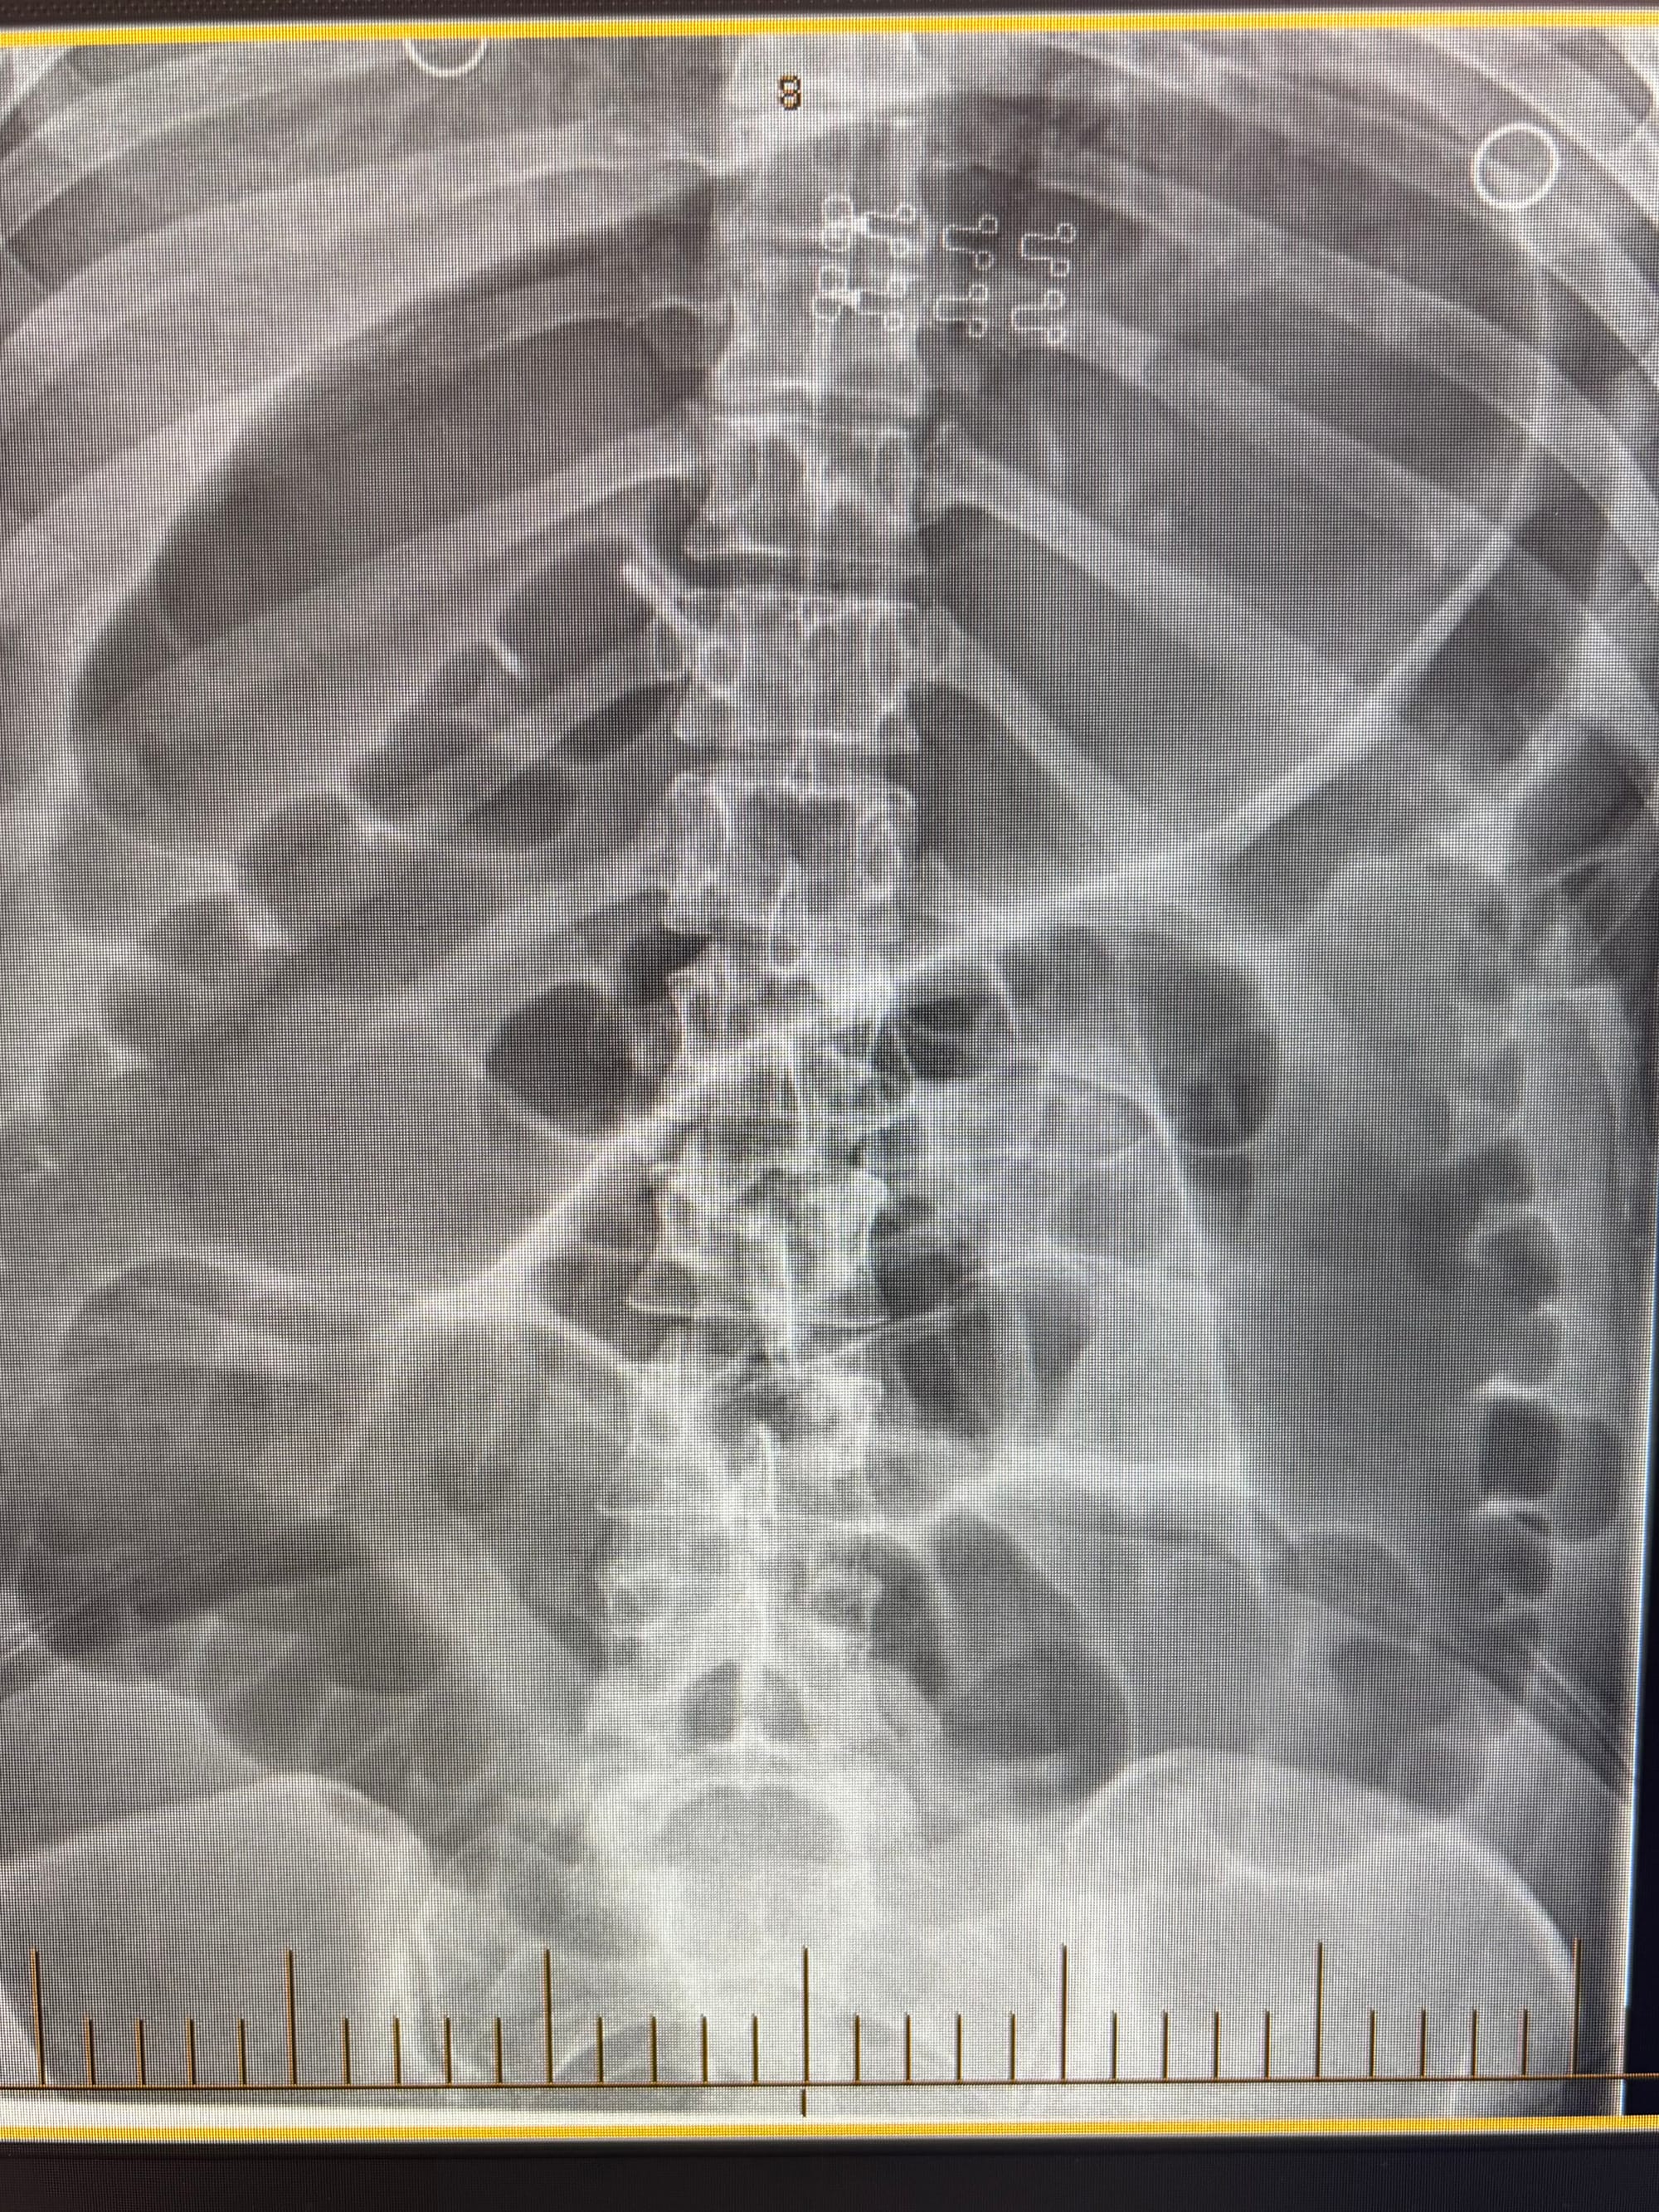

The clinical impression was of bowel obstruction. An abdominal X-ray showed dilated large bowel loops with a transverse diameter of 9 cm at the proximal transverse colon

The 3-6-9 rule is an aide memoire for the upper limit of normal bowel dimensions of small bowel, large bowel and caecum respectively.6